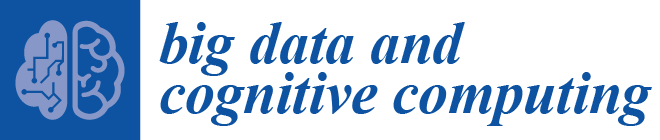

3. Methodology

3.1. Dataset and Preprocessing

3.2. Model Architecture

3.3. Training